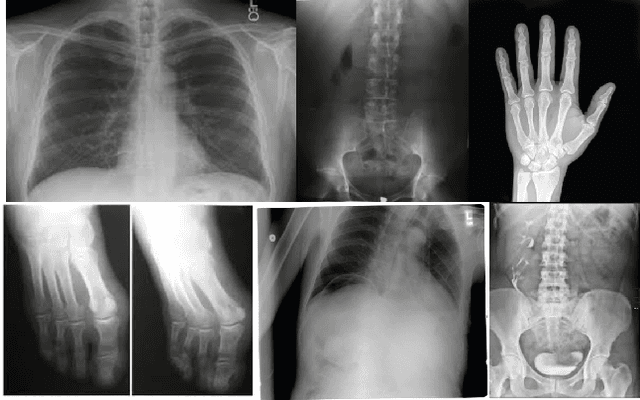

Abstract:Medical imaging is essential in healthcare to provide key insights into patient anatomy and pathology, aiding in diagnosis and treatment. Non-invasive techniques such as X-ray, Magnetic Resonance Imaging (MRI), Computed Tomography (CT), and Ultrasound (US), capture detailed images of organs, tissues, and abnormalities. Effective analysis of these images requires precise segmentation to delineate regions of interest (ROI), such as organs or lesions. Traditional segmentation methods, relying on manual feature-extraction, are labor-intensive and vary across experts. Recent advancements in Artificial Intelligence (AI) and Deep Learning (DL), particularly convolutional models such as U-Net and its variants (U-Net++ and U-Net 3+), have transformed medical image segmentation (MIS) by automating the process and enhancing accuracy. These models enable efficient, precise pixel-wise classification across various imaging modalities, overcoming the limitations of manual segmentation. This review explores various medical imaging techniques, examines the U-Net architectures and their adaptations, and discusses their application across different modalities. It also identifies common challenges in MIS and proposes potential solutions.